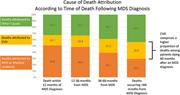

Depression, quality of life, and medical resource utilization in sickle cell disease

Depression, quality of life, and medical resource utilization in sickle cell disease